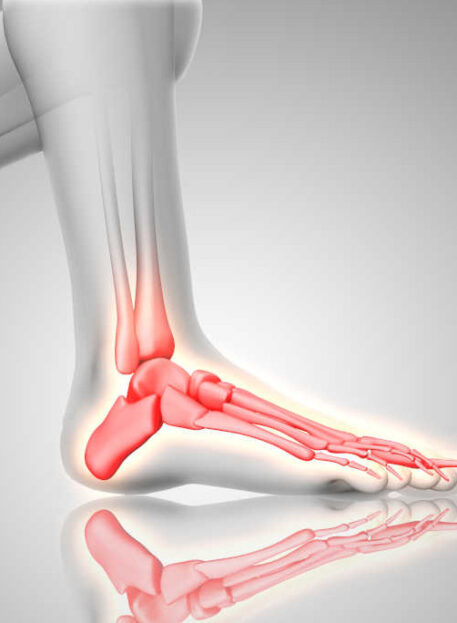

Spodnji (subtalarni) skočni sklep povezuje skočnico (talus) in petnico (kalkaneus). Ima omejeno gibljivost (do 40°) in omogoča predvsem gibanje stopala navznoter (varus) in navzven (valgus), pri čemer varus predstavlja približno dve tretjini giba.

01. Vzroki artritisa spodnjega skočnega sklepa

- Travmatske poškodbe (zlomi, izpahi, zvini)

- Revmatoidni artritis

- Dolgotrajna imobilizacija po zlomu kosti ali poškodbi Ahilove tetive

- Zapleti po operativnih posegih

02. Simptomi

- Bolečina v predelu spodnjega skočnega sklepa

- Tog občutek v stopalu

- Otekanje po daljšem obremenjevanju

- Težave pri hoji po neravnem terenu